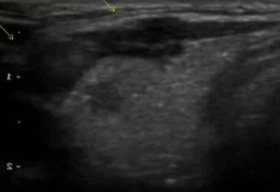

病例,44F 主动监测(wait and see)2年后,要求做甲状腺微创治疗。两次献血穿刺,一次发现包膜侵犯,确定外科治疗

![]() |